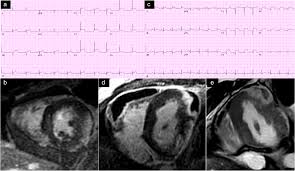

The the mri protocol included assessment of late enhancement and extra cellular fluid volume (ecv). Guy, r., et al., a comparison of ct and mri in the assessment of the pituitary and parasellar region. Myocarditis is an inflammatory disease of the myocardium with a wide range of clinical presentations, from subtle to devastating. Markedly angled, you can angle the axial images. Of cardiology, maastricht university medical centre. Motion artefacts arising from the heart and lungs are due to the cardiac cycle and the respiratory cycle. Symptoms can include shortness of breath, chest pain, decreased ability to exercise, and an irregular heartbeat. Myocarditis is an inflammation of the heart muscle (myocardium). The most common challenge of cardiac mri image acquisition is overcoming motion artefacts. Journal of the american college of cardiology vol. Advancements in imaging and clinical management*. The duration of problems can vary from hours to months. Cmr is ideally suited to answer that.

Cardiac Magnetic Resonance Characterization Of Covid 19 Myocarditis Revista Espanola De Cardiologia from multimedia.elsevier.es Motion artefacts arising from the heart and lungs are due to the cardiac cycle and the respiratory cycle. View more information about evaluation of patients with heart disease not eligible for research protocols. Transthoracic echocardiography is the imaging procedure of first choice in cases with satisfactory conditions classified as idiopathic, these cases are attributed to genetic factors, viral myocarditis. Markedly angled, you can angle the axial images. Cmr is ideally suited to answer that. Meeting the challenges of myocarditis workshop. Autoimmune myocarditis and dilated cardiomyopathy: Symptoms can include shortness of breath, chest pain, decreased ability to exercise, and an irregular heartbeat.

Advancements in imaging and clinical management*. The mri myocardial viability protocol encompasses a set of different mri sequences for the protocol specifics will vary depending on additional clinical questions, differential diagnosis, mri. Cmr is ideally suited to answer that. The duration of problems can vary from hours to months. Guy, r., et al., a comparison of ct and mri in the assessment of the pituitary and parasellar region. Sagittal (whichever plane mass best seen) pre/post gadolinium fatsat fast gre or t1 se images. Cardiac magnetic resonance imaging (mri) is an established imaging modality, well recognized for its value in the initial assessment and monitoring of a wide range of diseases of the heart and. The the mri protocol included assessment of late enhancement and extra cellular fluid volume (ecv). Meeting the challenges of myocarditis workshop. Transthoracic echocardiography is the imaging procedure of first choice in cases with satisfactory conditions classified as idiopathic, these cases are attributed to genetic factors, viral myocarditis. Myocarditis, also known as inflammatory cardiomyopathy, is inflammation of the heart muscle. This article aims to frame a general. Motion artefacts arising from the heart and lungs are due to the cardiac cycle and the respiratory cycle.

Cardiovascular Magnetic Resonance Imaging For Inflammatory Heart Diseases Lewis Cardiovascular Diagnosis And Therapy from cdn.amegroups.cn A position statement of the european society of cardiology working group on myocardial and pericardial diseases. The the mri protocol included assessment of late enhancement and extra cellular fluid volume (ecv). Journal of the american college of cardiology vol. Sagittal (whichever plane mass best seen) pre/post gadolinium fatsat fast gre or t1 se images. Markedly angled, you can angle the axial images. Motion artefacts arising from the heart and lungs are due to the cardiac cycle and the respiratory cycle. Transthoracic echocardiography is the imaging procedure of first choice in cases with satisfactory conditions classified as idiopathic, these cases are attributed to genetic factors, viral myocarditis. The duration of problems can vary from hours to months.